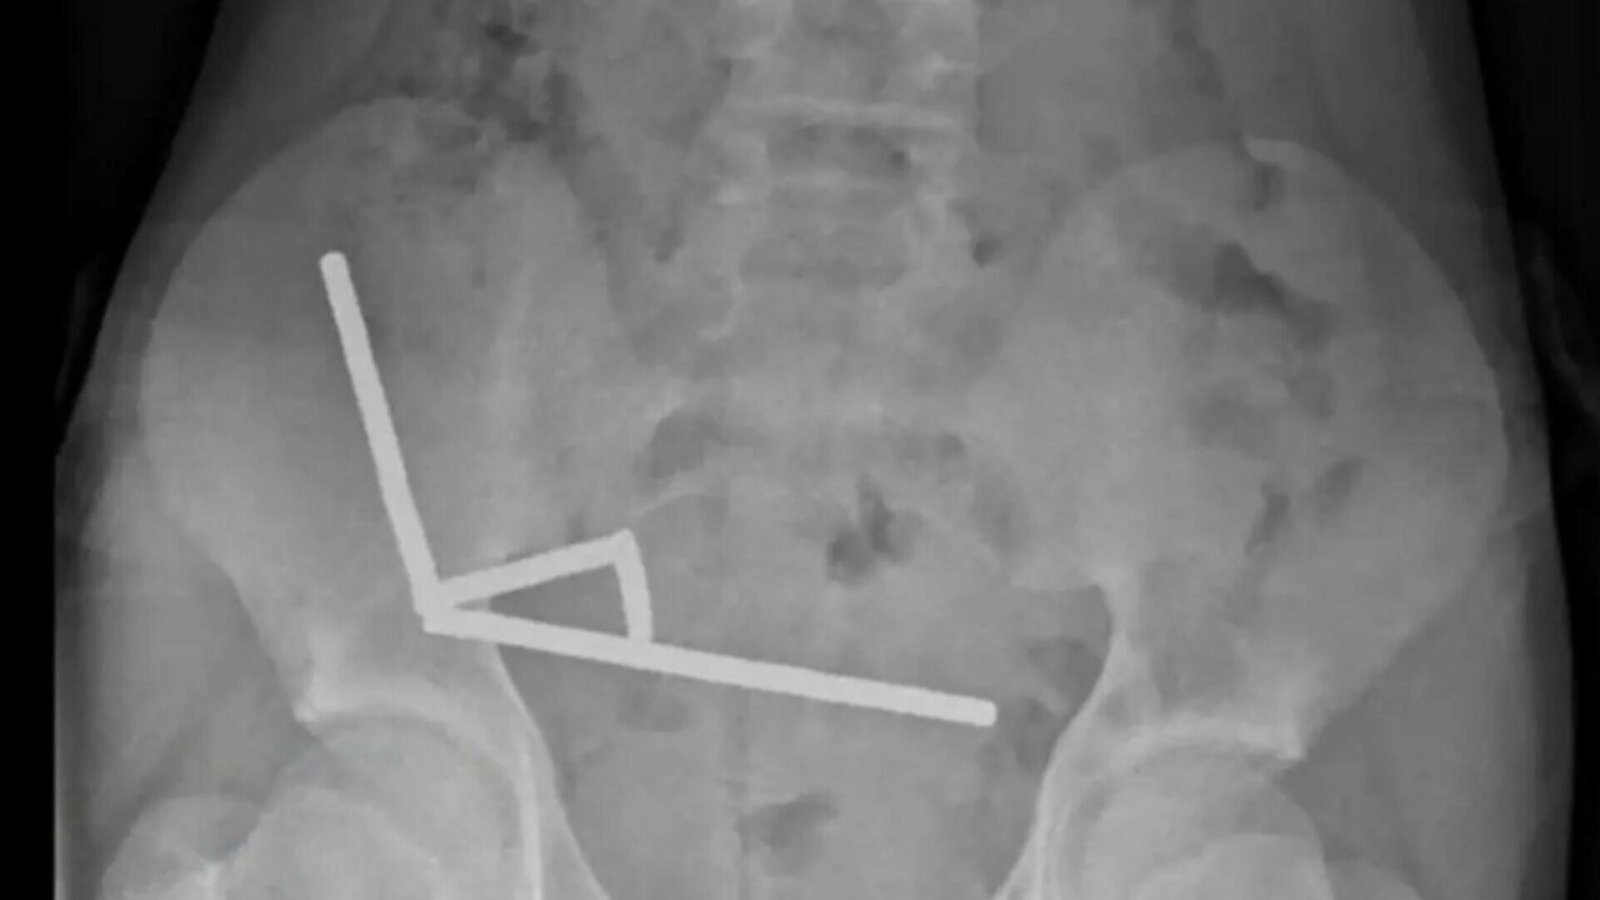

Intervenție de urgență pentru un adolescent de 13 ani după ce a ingerat aproape 200 de magneți

Incident grav: adolescent de 13 ani operat după înghițirea a aproape 200 de magneți…